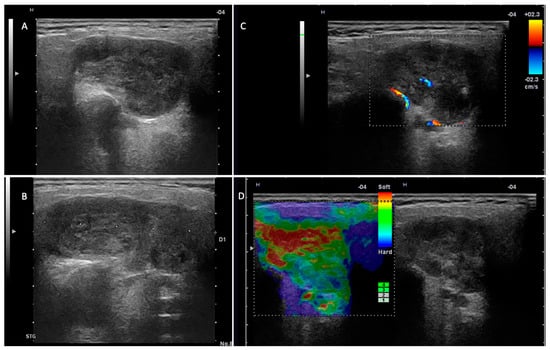

- Stoia, S.; Băciuț, G.; Lenghel, M.; Badea, R.; Băciuț, M.; Bran, S.; Dinu, C. Ultrasonography techniques in the preoperative diagnosis of parotid gland tumors—An updated review of the literature. Med. Ultrason. 2021, 23, 194–202. [Google Scholar] [CrossRef]

- Rzepakowska, A.; Osuch-Wójcikiewicz, E.; Sobol, M.; Cruz, R.; Sielska-Badurek, E.; Niemczyk, K. The differential diagnosis of parotid gland tumors with high-resolution ultrasound in otolaryngological practice. Eur. Arch. Oto-Rhino-Laryngol. 2017, 274, 3231–3240. [Google Scholar] [CrossRef] [PubMed]

- Fischer, T.; Paschen, C.F.; Slowinski, T.; Alkhameri, A.; Berl, J.C.; Klingebiel, R.; Thomas, A. Differentiation of parotid gland tumors with contrast-enhanced ultrasound. Fortschr. Röntgenstr. 2010, 182, 155–162. [Google Scholar] [CrossRef]

- Rong, X.; Zhu, Q.; Ji, H.; Li, J.; Huang, H. Differentiation of pleomorphic adenoma and Warthin’s tumor of the parotid gland: Ultrasonographic features. Acta Radiol. 2014, 55, 1203–1209. [Google Scholar] [CrossRef]

- Mansour, N.; Stock, K.F.; Chaker, A.; Bas, M.; Knopf, A. Evaluation of parotid gland lesions with standard ultrasound, color duplex sonography, sonoelastography, and acoustic radiation force impulse imaging—A pilot study. Ultraschall Med. 2012, 33, 283–288. [Google Scholar] [CrossRef] [PubMed]

- Matsuda, E.; Fukuhara, T.; Donishi, R.; Kawamoto, K.; Hirooka, Y.; Takeuchi, H. Usefulness of a novel ultrasonographic classification based on anechoic area patterns for differentiating warthin tumors from pleomorphic adenomas of the parotid gland. Yonago Acta Med. 2017, 60, 220–226. [Google Scholar] [CrossRef] [PubMed]

- Białek, E.J.; Jakubowski, W.; Karpinska, G. Role of Ultrasonography in Diagnosis and Differentiation of Pleomorphic Adenomas. Arch. Otolaryngol. Head Neck Surg. 2015, 129, 929–933. [Google Scholar] [CrossRef][Green Version]